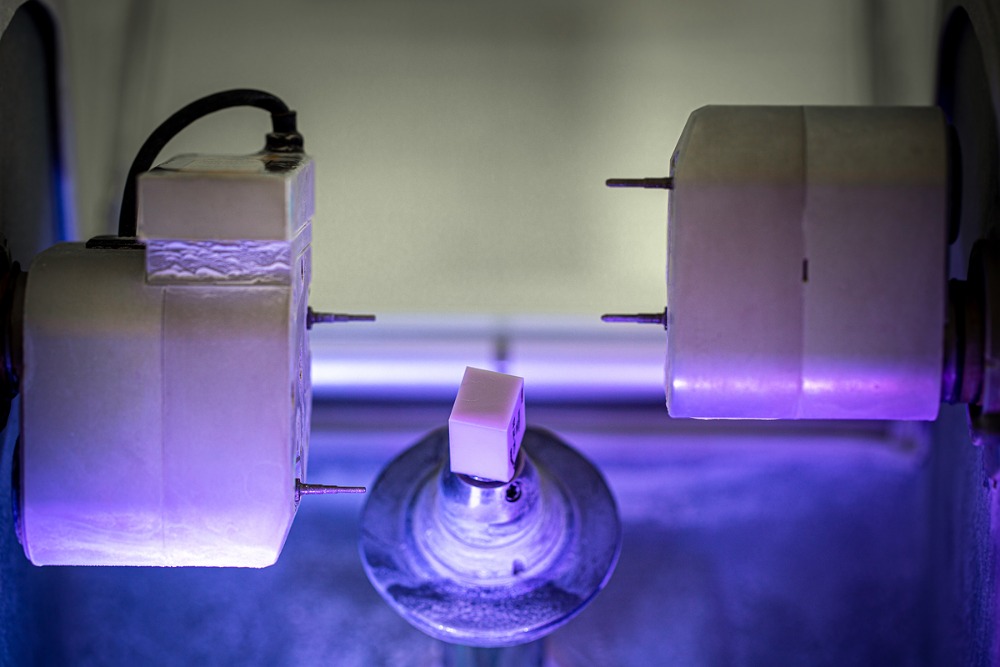

Výroba estetických celokeramických korunek dle sceneru, individuálně pro každého jednotlivého pacienta, dle vzhledu, fyziognomie obličeje a genetiky zubů.